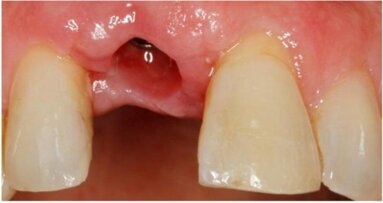

Badanie grubości tkanki kostnej wyrostka zębodołowego w znieczuleniu miejscowym i poprzeczne skany DTS dały obraz odmienny (Ryc. 6). Wobec wymiaru poprzecznego kości 2,6 mm zastosowano wszczepy igłowe o śr. 1,5 mm. Wprowadzono je bez otwierania płata, w znieczuleniu nasiękowym na szczycie wyrostka niewielką ilością 4% artykainy, zgodnie z przytoczoną metodologią (Ryc. 7). Ustabilizowane wszczepy połączono naddziąsłowo prętami tytanowymi o takiej samej średnicy za pomocą zgrzewarki wewnątrzustnej Mondaniego. Wolne przestrzenie uzupełniono kompozytem, powstałe pełne struktury oszlifowano, nadając im kształt filarów protetycznych (Ryc. 8) i pobrano wyciski do ostatecznych koron porcelanowych. Zabieg zakończono zacementowaniem przygotowanych w gabinecie prowizorycznych koron kompozytowych (Ryc. 9 i 10).